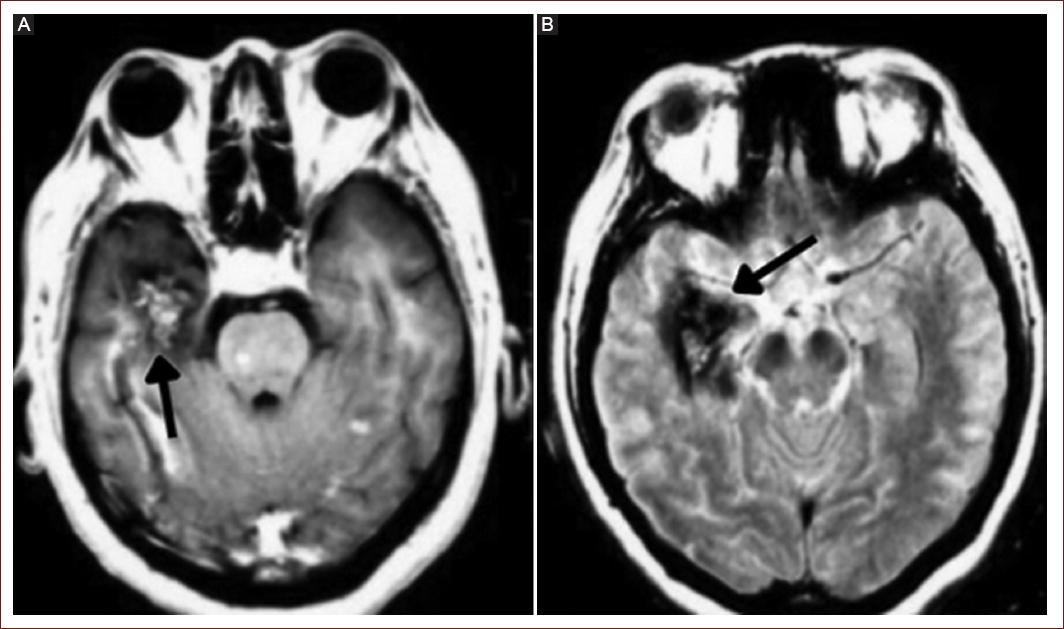

Embolism can lead to the development of ischemic cerebral infarctions (Fig. 2). In patients with myxoma, systemic embolism occurs in 30-50% of cases, with 50% of those embolizations affecting the central nervous system and the retinal artery. This is attributed to the biological ability of myxoma to detach and cause embolization or to the tumor's morphology, especially when it has an external velvety appearance, which independently increases the risk of embolism (OR = 8.7; 95% confidence interval [CI]: 2.4-42.1; p < 0.001)9.

Figure 2 Cerebral magnetic resonance imaging. A and B: cerebral metastases are shown in the right temporal lobe.